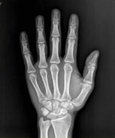

医学影像学是一门理论性和实践性均很强的应用科学,包括X线、超声、MRI、核医学及介入影像学等。主要用于临床的各种疾病的诊断和治疗,是影像医学生必需掌握的一门课程,是成为一名合格影像医生的必备技能。

学习医学影像学是为了诊疗疾病有正确的保证。影像学诊断是对疾病进行较精确定位、定性及定量今断的学科,是临床的常规检查,已使过去不能诊断的疾病得到了早期适时正确的诊断和治疗。影像技术的应用在一定程度上决定了医疗水平的高低,关系到临床各科室各种疾病的诊断,临床医学对影像诊断的依赖性越来越大。因此,掌握好各种影像检查方法的适应症以及各种基本病变的表现是正确作出最恰当诊疗的保证。